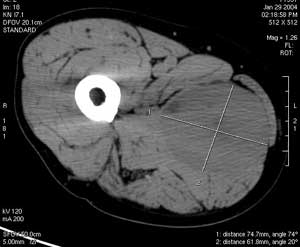

CT

能對各部位腫瘤精確定位,尤適於腹腔,盆腔,顱內及頭顱部腫瘤。

CT表現無特徵性,橫紋肌肉瘤表現結節狀有分隔軟組織腫塊或呈膨脹性團塊不均密度陰影,大部分病變密度低於肌肉,部分病例腫瘤病變有較高密度,厚度不均的環形密度影。